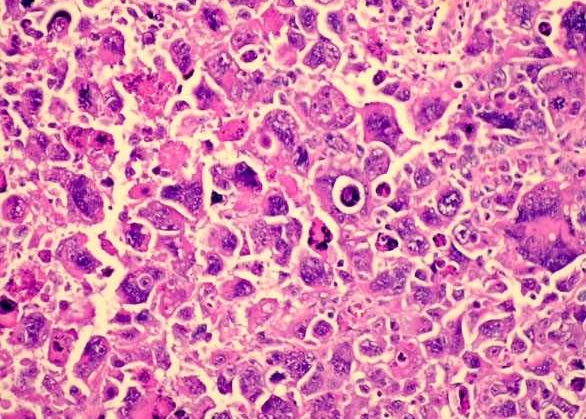

- Альвеолярная – внутри данного рода опухоли есть соединительные перегородки, к которым присоединяются опухолевые клетки разных видов (крупные, вытянутые, многоядерные) и т.д. Опухоль располагается в мягких тканях различных органов. Этот вид рабдомиосаркомы возникает в основном молодом возрасте;

- Плеоморфная рабдомиосаркома одна из самых распространенных видов, которая может достичь больших размеров. Эта опухоль развивается в основном в нижних конечностях. При рассмотрении с помощью специального оборудования, можно увидеть, что образование состоит из клеток, которые имеют разные формы (грушевидные, ленточные, круглые);